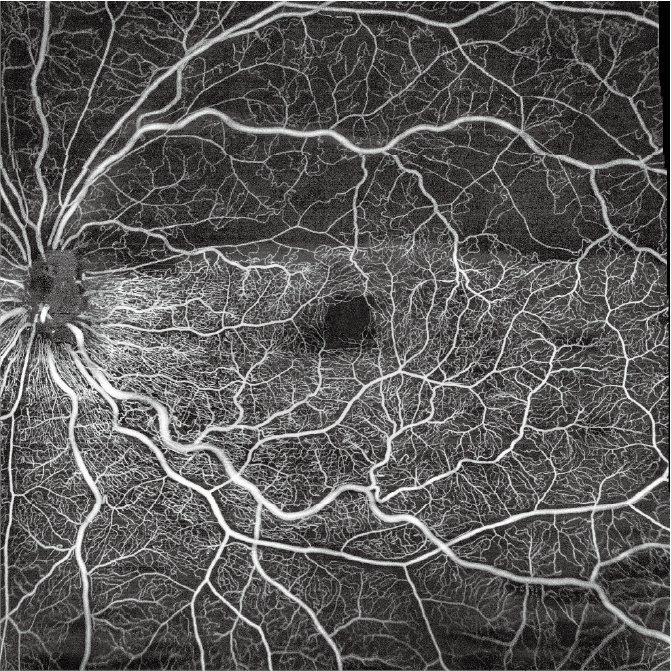

- 15mm x 15mm Wide-field OCTA

- Choroid OCTA with Quantification Parameters